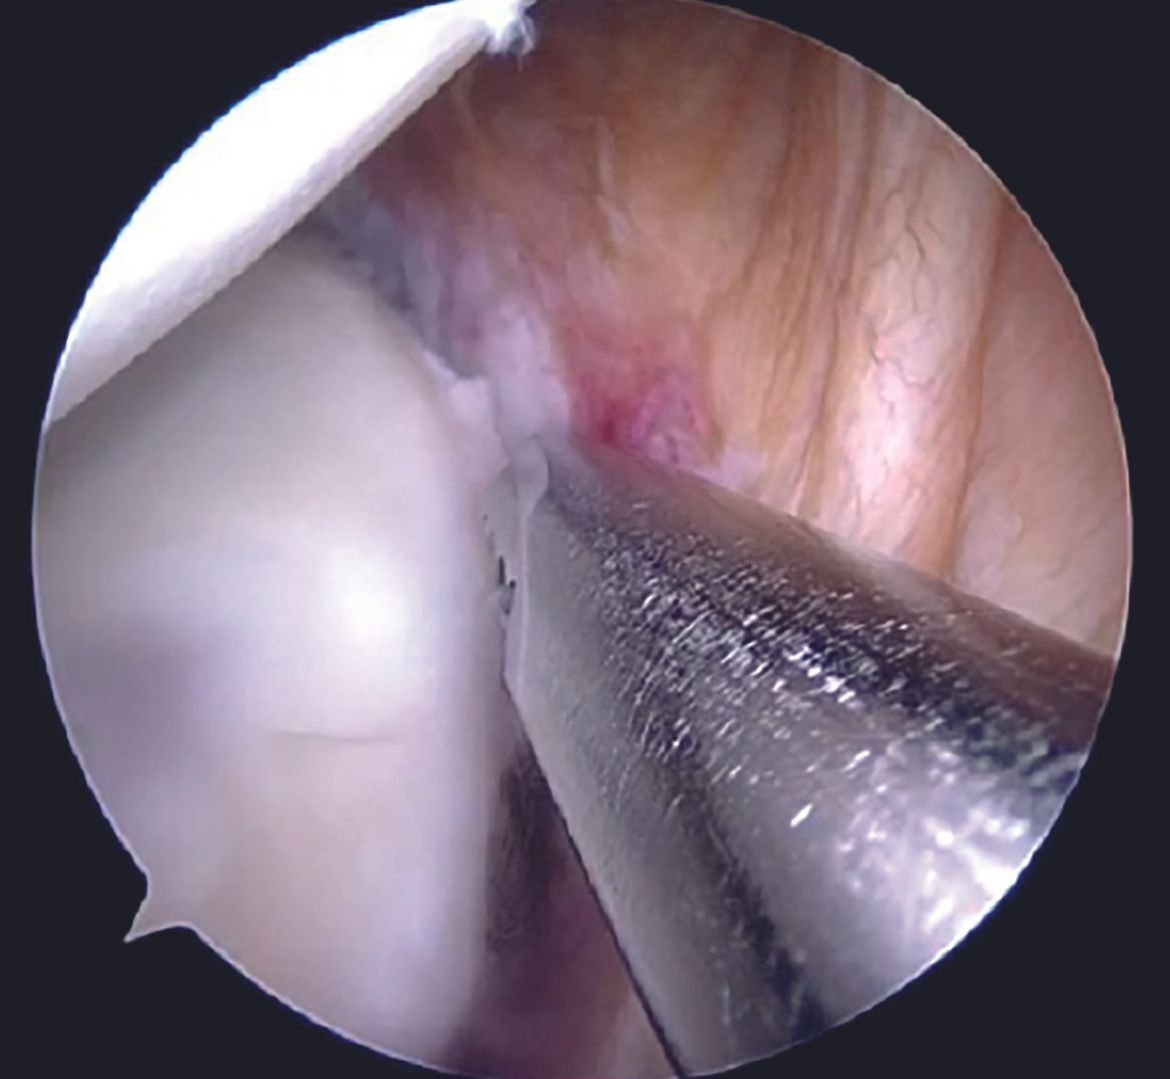

After the diagnostic arthroscopy, viewing portal is switched to the anterosuperior one, whereas the anteroinferior and the posterior portals act as the working portals with 7mm and 5mm cannulae, respectively. Labral tear extent is assessed with a probe (Figure 5).

Capsulolabral tissue is mobilized using 15 and 30 degree arthroscopic tissue elevators sequentially (Figure 6).